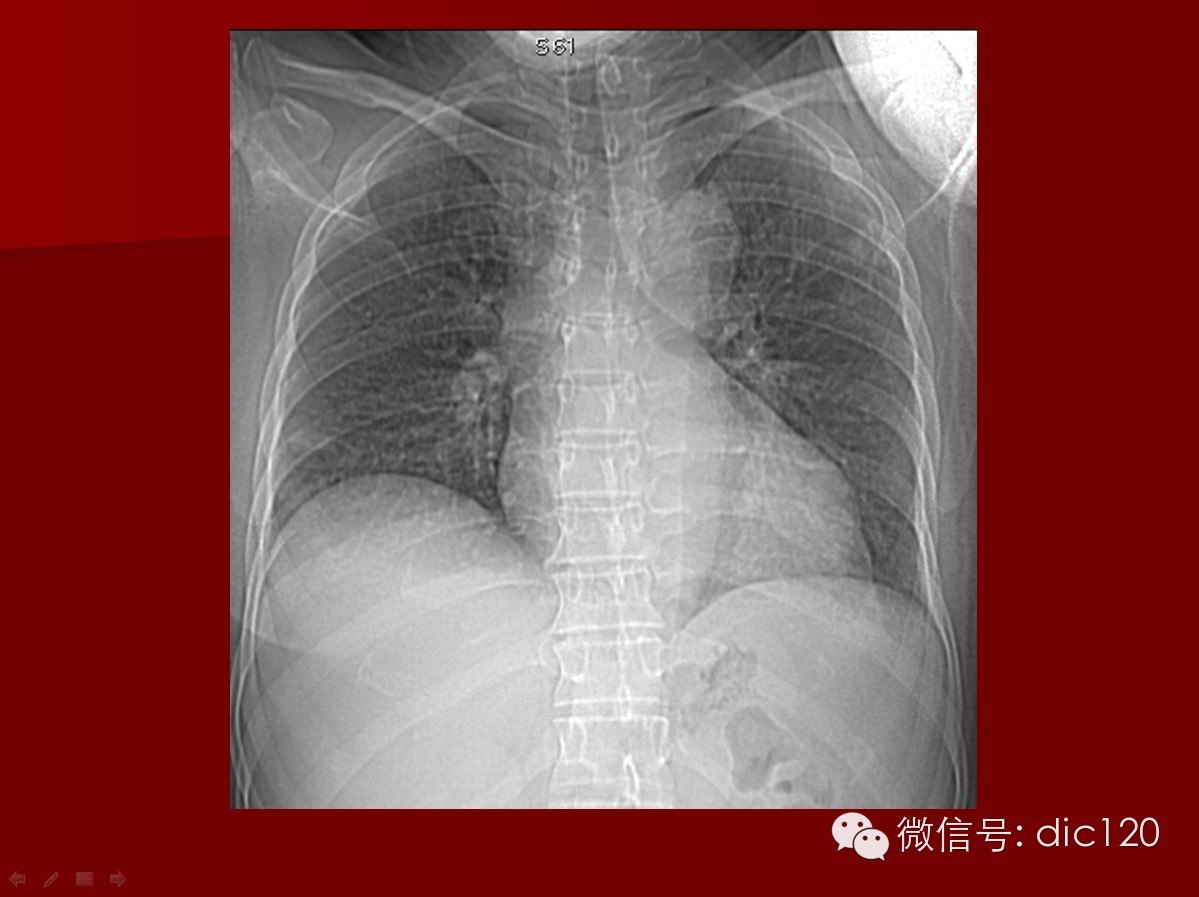

2.胸片异常 胸片示结节、固定浸润病灶或空洞

本病影像肺内表现特征:1)结节、球形肿块及空洞:病灶可单发也可多发,病灶多见于两肺下叶,也可位于肺尖,且肺外带好发,2/3病例球形肿块内出现空洞,洞壁较厚、不规则,其中可见液平,用免疫抑制剂及肾上腺皮质激素治疗,病灶可缩小或消失,病情恶化时可出现新病灶。斑片状影:较为少见,为肺血管炎引起的肺出血和肺梗死,合并炎症也可出现,病灶较大可占据一个肺段,病灶可在1~2周内缩小或消失,但又可出现新的病灶。